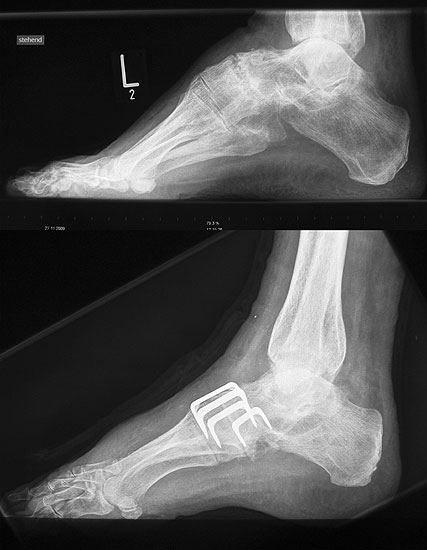

Lateralisierende Calcaneus-Osteotomie (Abb. 2 und 3, Video 2)

Die lateralisierende Calcaneus-Osteotomie ist ein Standard-Operationsschritt bei fast jeder Hohlfuβkorrektur. Der biomechanische Effekt der Osteotomie ist eine Verschiebung des Fersenkontaktpunktes und damit der beim Rückfuβ varus medialisierten Belastungsachse durch das OSG nach lateral. Diese statische Rückfuβ-Korrektur allein ist in der Lage, den bei Pes cavovarus anteromedial erhöhten OSG-Druck, der sehr wahrscheinlich zur korrespondierenden Arthrose führt, zu neutralisieren 7. Zuklappende Osteotomien mit Entnahme eines lateralen Knochenkeils haben sich dabei weniger effektiv gezeigt als solche mit Lateralisation des Tubers. Mit der Lateralisation des Achilles-Ansatzes verringert sich die Inversionskraft der Sehne zugunsten der schwachen Eversion, wodurch gleichzeitig die Prädisposition für Supinationstraumata reduziert wird. Neben der klassischen Dwyer-Osteotomie (Entnahme eines lateralen, vertikalen Keils 8 haben sich vor allem die technisch einfache Verschiebe-Osteotomien („sliding osteotomy“) und die Z-förmigen Osteotomien (Pisani 1993, Malerba 9) mit Entnahme eines lateralen Keils aus dem horizontalen Anteil der Osteotomie aber ohne Lateralisation des Tuberfragmentes, sowie die Korrektur nach Hintermann (Knupp 2008) mit zusätzlicher Lateralisation des Tuberfragmentes) durchgesetzt. Bei neutral aligniertem OSG ist keine supramalleoläre Tibia-Osteotomie zur Korrektur des Rückfuβ varus indiziert. Generell sollten Osteotomien gegenüber korrigierenden Arthrodesen der Vorzug gegeben werden. Die im Folgenden beschriebene Verschiebeosteotomie ist technisch einfach und hinsichtlich OSG-Druckneutralisation ebenso effektiv wie die Z-Osteotomien 7.

• Kontrolle der korrekten Schraubenlage im BV (Abb. 3).